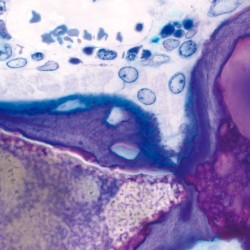

Maxresorb ® es un material sustituto óseo innovador, seguro, confiable y totalmente sintético que se caracteriza por una reabsorción controlada y excelentes características de manipulación. maxresorb ® está compuesto por un 60% de hidroxiapatita (HA) de lenta absorción y un 40% de beta-fosfato tricálcico (β-TCP) de rápida absorción 1,2 . El exclusivo proceso de producción basado en síntesis garantiza una distribución completamente homogénea de ambas fases minerales. La composición especial de maxresorb ® promueve la rápida formación de nuevo hueso vital y asegura una reabsorción controlada sin pérdida de volumen del sitio aumentado.

Maxresorb ® es un material sustituto óseo innovador, seguro, confiable y totalmente sintético que se caracteriza por una reabsorción controlada y excelentes características de manipulación. maxresorb ® está compuesto por un 60% de hidroxiapatita (HA) de lenta absorción y un 40% de beta-fosfato tricálcico (β-TCP) de rápida absorción 1,2 . El exclusivo proceso de producción basado en síntesis garantiza una distribución completamente homogénea de ambas fases minerales. La composición especial de maxresorb ® promueve la rápida formación de nuevo hueso vital y asegura una reabsorción controlada sin pérdida de volumen del sitio aumentado.

Porosidad interconectada ultra alta

La osteoconductividad de maxresorb ® se basa en una red de poros interconectados, una porosidad total muy alta de aprox. 80% así como su superficie muy rugosa 3, 4, 5 . La superficie nanoestructurada facilita la adsorción de sangre, proteínas y células madre y promueve la diferenciación celular y la integración ósea. maxresorb ® es, por lo tanto, un andamio ideal para la migración de células formadoras de hueso y la unión de moléculas de señalización, que pueden acelerar la integración y regeneración del tejido 6, 7 .